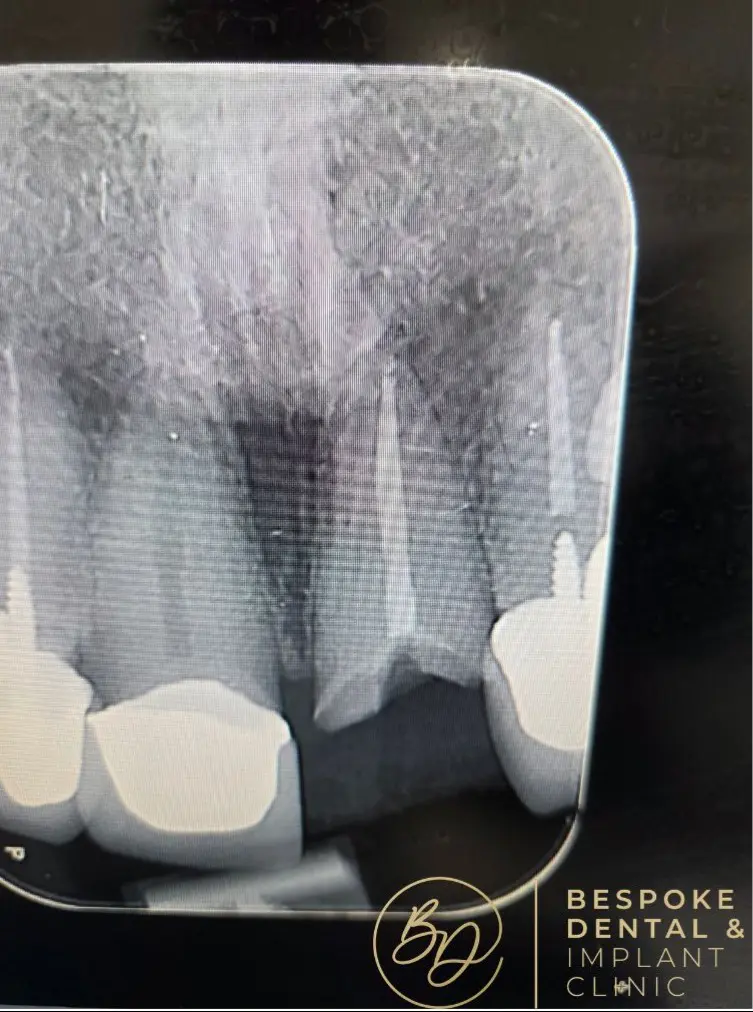

A dental implant is a screw-like metal post inserted into the jawbone. It acts as a natural tooth root and serves as a foundation for the replacement tooth, a custom-made dental crown that sits atop the implant.